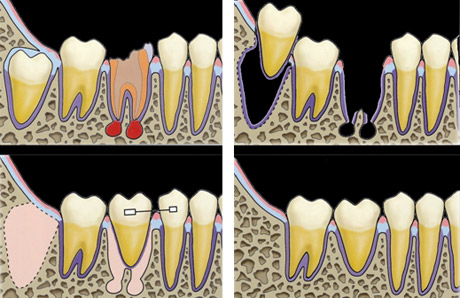

歯根完成歯親知らずの移植

左:治療前のCT画像。

24歳、女性。右下第二大臼歯部(受容側)へ親知らず(ドナー歯)を移植してほしいという希望で来院されました。

ドナー歯はすでに歯根が完成しています。このような場合、移植後に歯髄(神経)の治療が必要です。

左:移植のために抜歯された親知らず(ドナー歯)。

右:移植直後。

左:移植直後のエックス線写真。

右:移植後1ヶ月。

根管治療直後。歯根が完成している歯を移植歯として用いた場合、歯の神経はつながらないので、このように神経の治療が必要になります。

移植後4ヶ月。

移植歯はコンポジットレジンで修復が行われています。